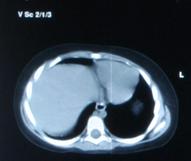

Fig. nr. 270. Formatiunea tumorala explorata echo in figura anteorioara, acum la computer tomografie, in raport cu ficatul. Intraoperator s-a gasit un teratom retroperitoneal.